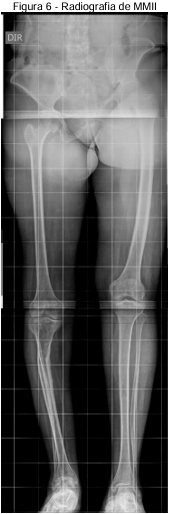

Em radiografia panorâmica de membros inferiores e escanometria apresenta os seguintes resultados: Textura óssea reduzida, notadamente a direita; Afilamento do fêmur, tíbia e fíbula a direita; Encurvamento da diáfise da tíbia direita; Avançadas alterações degenerativas do tornozelo a direita; Hipotrofia da musculatura a direita e Infradesnivelamento da asa ilíaca direita em cerca de 6 cm (Figuras 4, 5 e 6).

Fonte: Prontuário médico (2024)